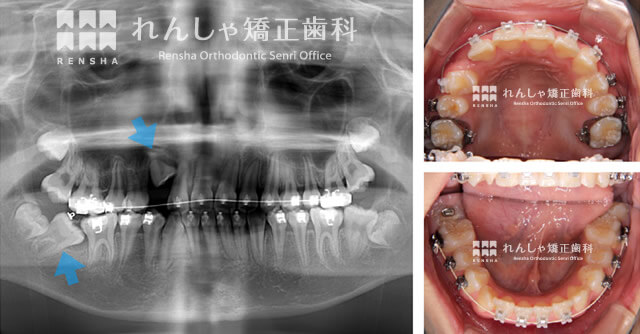

装置をつけて右上犬歯と右下奥歯が出やすい環境をつくる

ご紹介の症例写真は、右上犬歯と右下奥歯が出やすい環境をつくる際のものです。

歯列を拡大すると、前歯は少しずつ外側に移動します。Y.Kさんによるとその影響もあって、当時は特に下唇の口内炎に悩まされた、ということでした。

埋まったままになっている原因がスペース不足であれば、そのスペースを確保することで引っ張り出すことは可能です。

ただ人によって、周りの骨に引っかかっていたり、骨と癒着している場合もあります。この様な場合は牽引に時間がかかったり、引っ張り出せないことも…。

ただ幸いなことに、Y.Kさんの治療では無事引っ張り出すことができました。